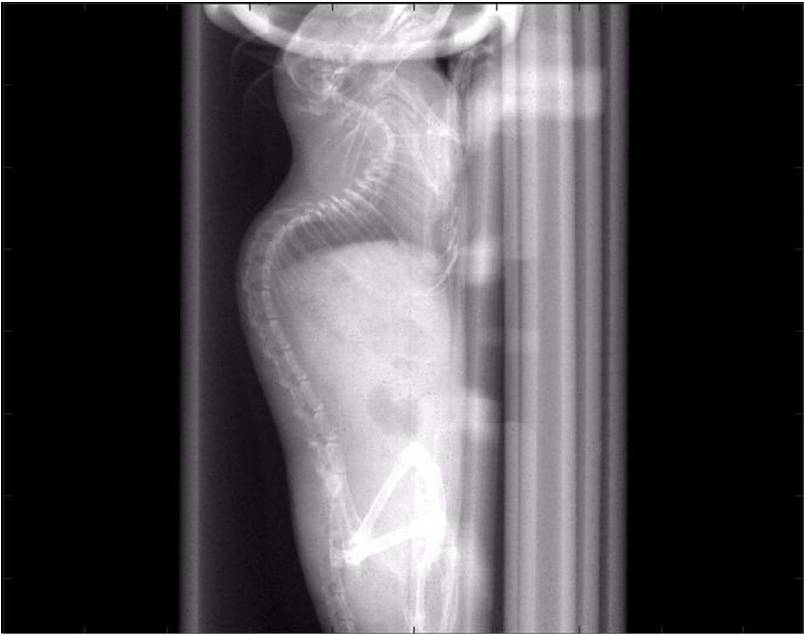

檢測(cè)案例

小鼠股骨

超高分辨率模式下像素大小為9μm。

A軸向和矢狀面顯示小鼠股骨結(jié)構(gòu)。

B用鈦材料植入的穿過(guò)骨頭的冠狀切片